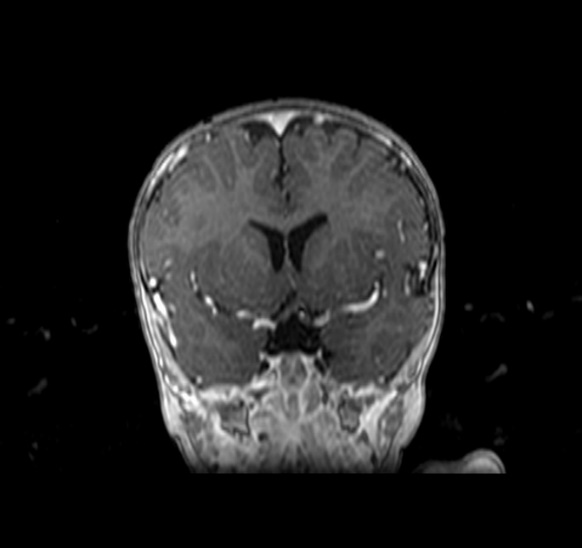

MRI findings showed the lack of the normal flow void of the left internal carotid canal and the first part of the left middle cerebral artery (Figures 1 and 2). The pituitary gland is flat. No evident anterior or posterior pituitary gland tissue or pituitary stalk is observed. The pituitary gland's strong posterior signal is not detected in situ or

ectopic. The left medial cerebral artery originates within the posterior circulation, and the left internal carotid artery cannot be seen. No intra, supra, retro or parasellar masses. Normal MRI appearance of the optic chiasm and corpus callosum. Otherwise, normal MR appearance of the brain parenchyma with no definite focal lesions. Diagnosis of congenital panhypopituitarism associated with agenesis of ICA was made.

a)

b)

c)

d)

Figure 1. a-c) figures showing MRI brain sagittal views of the patient where the pituitary sella is flat. No obvious anterior or posterior pituitary gland tissue or pituitary stalk is seen. The posterior pituitary bright signal is not visualized in site or ectopic. d) coronal MRI scan showing absence of pituitary gland tissue.

Generally, no intra, supra, retro, or parasellar masses. Normal MRI appearance of the optic chiasm and corpus callosum. Otherwise, normal MR appearance of the brain parenchyma with no definite focal lesions.